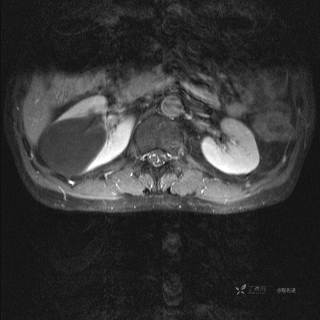

T1增强横断位